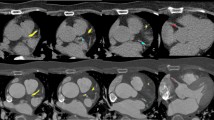

To automatically detect and quantify CAC, a novel algorithm was used to identify the presence of calcium in the coronary arteries. A reference trend line on the lumen intensity values along the centerline was fitted for each individual vessel, ranging from the proximal to the distal part of the vessel. After this, only the pixels near the centerline with intensity values higher than the reference trend line are considered to be calcified and selected for further processing using and advanced region growing scheme (Fig. 1.)

Fig. 1 Method for automatic coronary calcium detection. Example of the method for automatic coronary calcium detection. a An MPR with two calcified coronary lesions (white arrows). c Demonstrates the luminal intensities plot. The x axis represents the distance from the coronary ostium, the y axis represents the peak intensity along the centerline (HU). The red line is the trendline of this plot. Large deviations from this trendline are considered coronary calcium (white arrows). b Demonstrates a cross-sectional view of the coronary artery with the detected coronary calcium marked in blue. The yellow line indicates the coronary lumen border